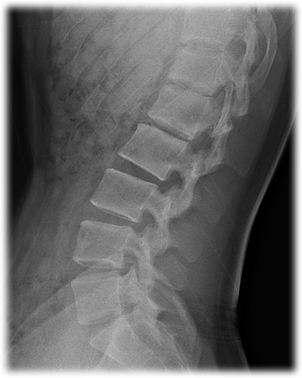

▪ 요추 X-ray 영상에서 L1~L4에 한 개의 질환(Normal, Osteopenia, Osteoporosis)이 라벨링 되어 있는 데이터셋으로 남녀 성비, 질환 분포의 다양성을 확보한 데이터 ▪ 전문의들이 X-Ray 영상과 진단데이터를 활용하여 판독한 골다공증 관련 서비스 활용에 신뢰성 있는 데이터

1. 대표이미지